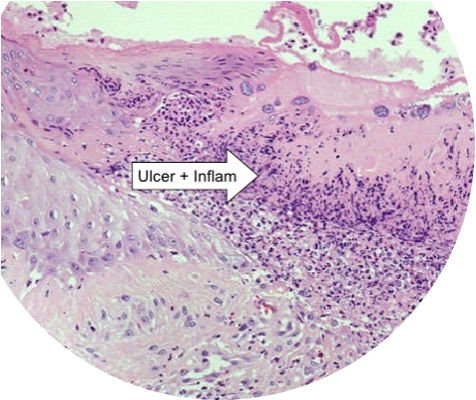

Ulcers covered by fibrino-necrotic exudate.

Intra-cytoplasmic eosinophilic inclusion bodies within keratinocytes